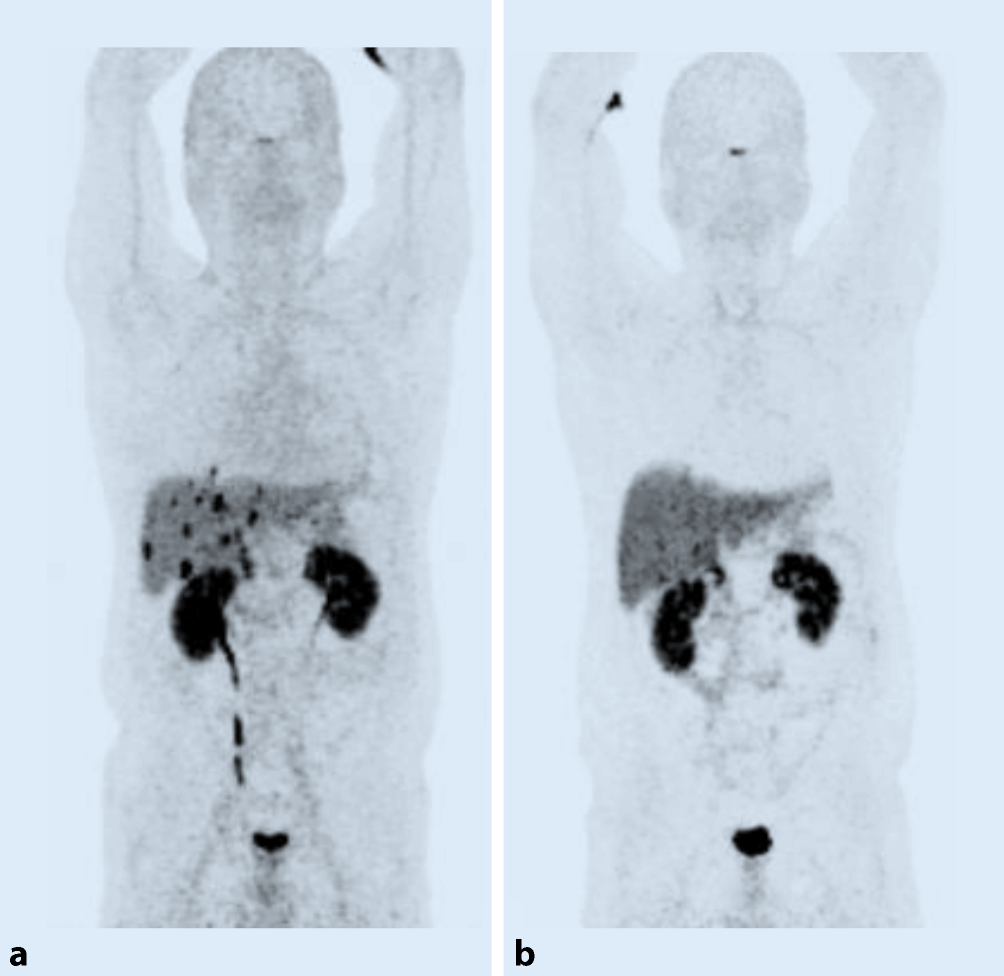

Die PRRT ist indiziert für die systemische Behandlung von SSTR-positive NET im metastasierten bzw. inoperablen Stadium [5]. In erster Linie betrifft dies NET, ausgehend vom gastroentero-pankreatischen (GEP) System bzw. vom Bronchialsystem. Diese Therapie wird vor allem bei niedriggradigen Tumorentitäten – Grad-1- und Grad-2-Tumoren – angewendet. Eine wesentliche Voraussetzung ist eine suffiziente Radionuklidaufnahme in den bekannten Tumormanifestationen, welche mithilfe der nuklearmedizinischen Bildgebung vor einer geplanten Therapie evaluiert werden muss. Der Nachweis einer vermehrten in vivo SSTR-Expression erfolgt im klinischen Alltag hauptsächlich mittels PET-CT-Diagnostik unter Verwendung eines Gallium-68 markierten SSTA, z. B. 68 Ga-DOTATOC. Eine Traceranreicherung intensiver als die Speicherung in der Leber spricht für eine ausreichende Rezeptorexpression (Abb. 1). Des Weiteren wird diese nuklearmedizinische Diagnostik auch für die Verlaufskontrolle nach erfolgter Therapie angewendet.

Abb. 1

Zweiundfünfzigjähriger Patient mit einem neuroendokrinen Tumor des Pankreas: Dieser Patient wurde bei Zustand nach Pankreasteilresektion, Splenektomie und Lebermetastasenresektion bei progredienter Tumorerkrankung zur weiterführenden Radionuklidpeptidtherapie (PPRT) zugewiesen. Die Ausgangsuntersuchung mittels 68Ga-DOTA-NOC PET-CT (a) im November 2015 zeigte eine intensive Speicherung der bekannten Lebermetastasen. Daraufhin wurde eine PRRT mit 3 Einzelgaben von 90Y-DOTA-TOC mit einer Gesamtaktivität von 11 GBq durchgeführt. Die Verlaufs-PET-CT-Untersuchung (b) im Mai 2016 zeigte ein deutliches Therapieansprechen in Bezug auf die Lebermetastasen